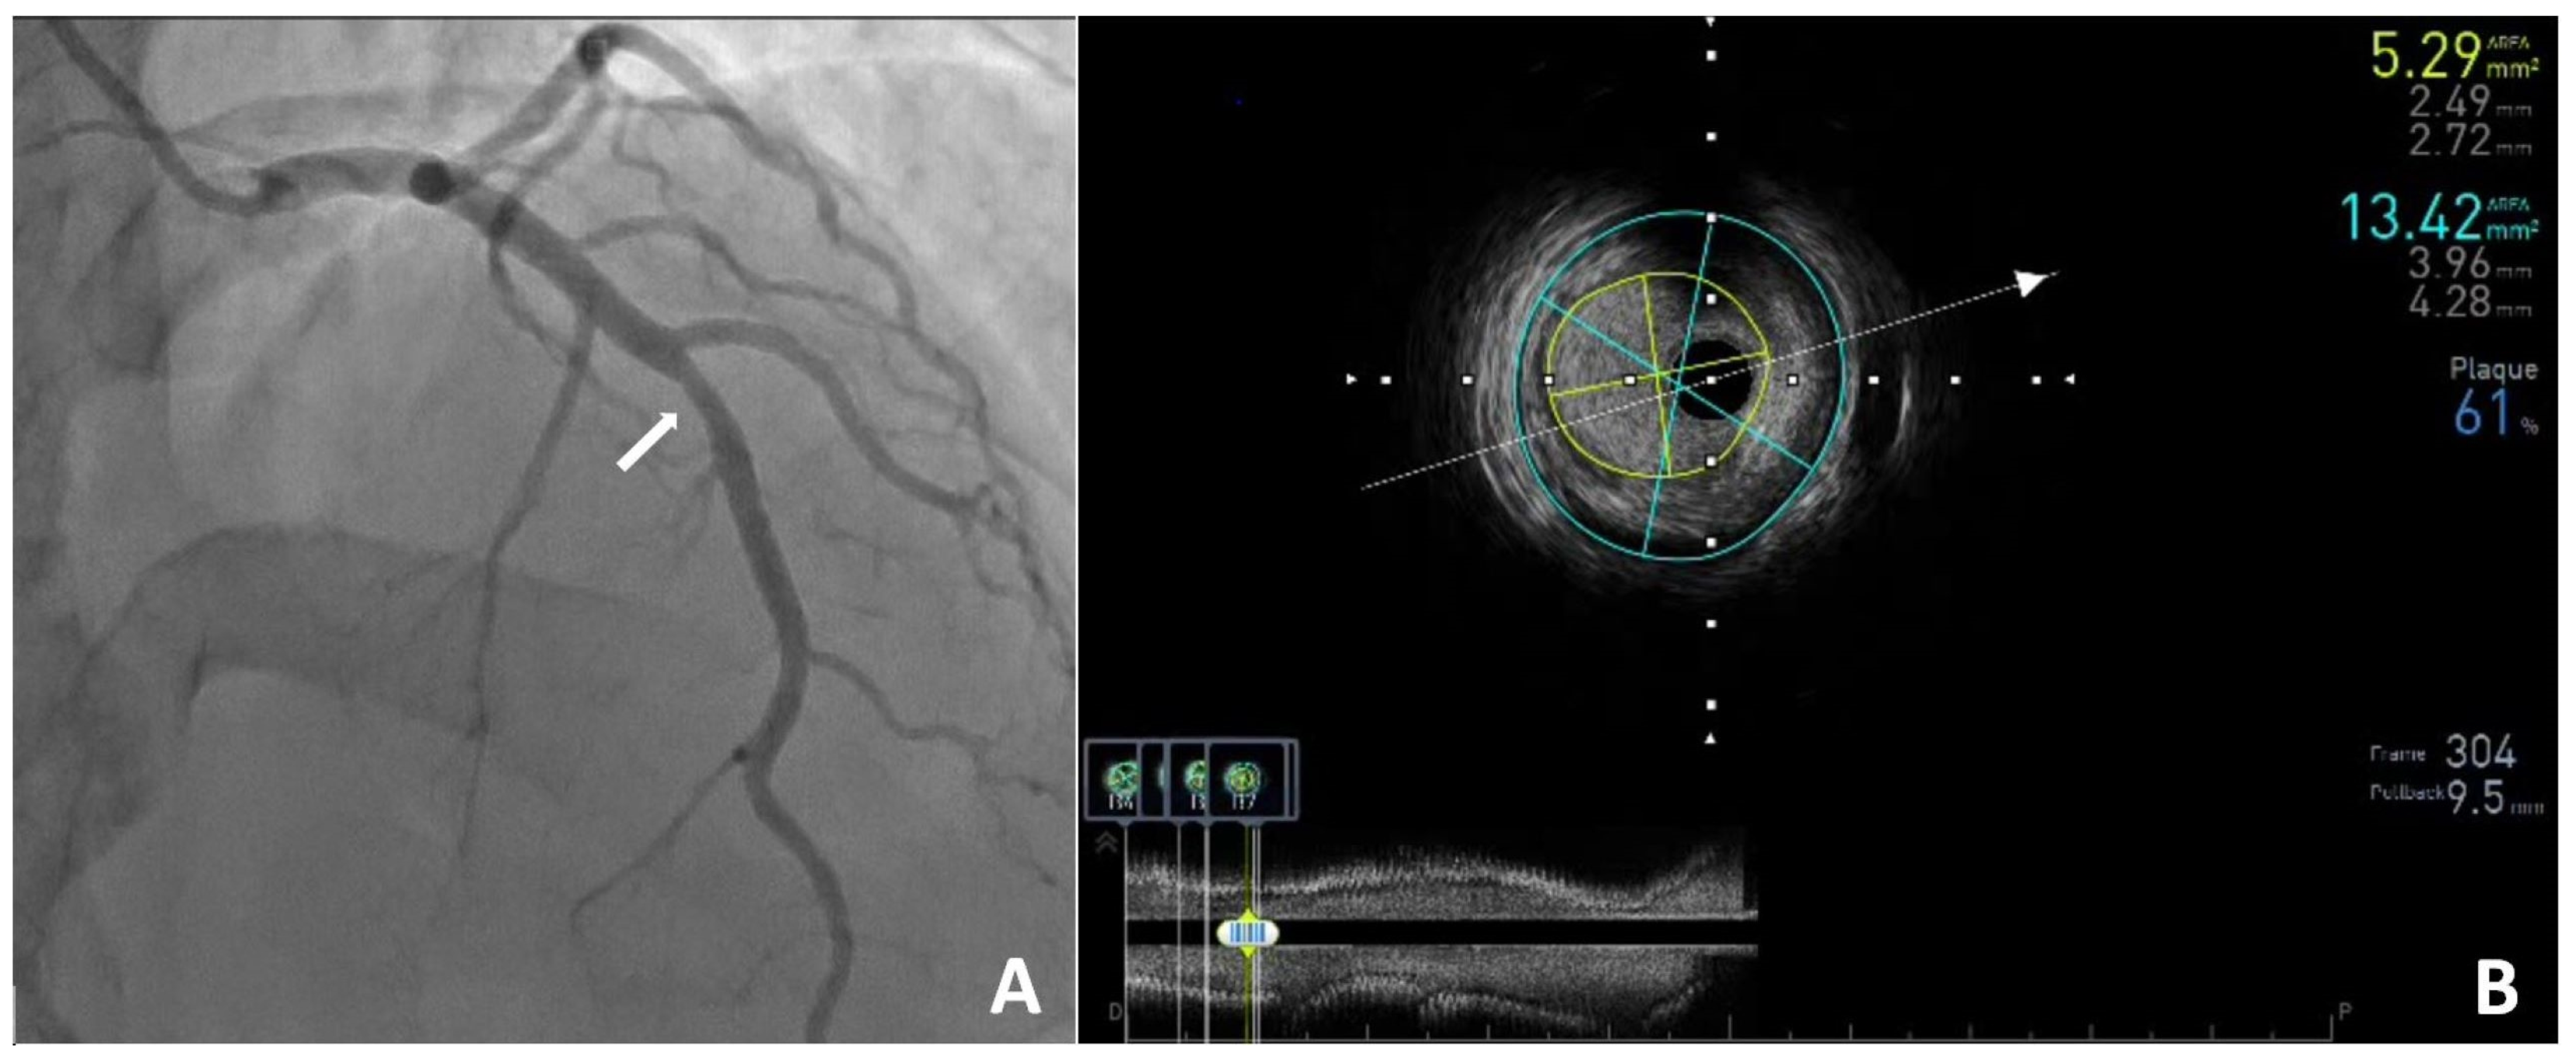

Computed Tomography, Coronary Angiography, and Intravascular Ultrasound in the Diagnosis of Left Anterior Descending Stenosis in a 38-Year-Old Woman with a Calcium Score of Zero

- Wojciechowski, A.; Zarotyńska, M.; Chyrchel, B.; Terlecki, M.; Wojciechowska, W.; Rajzer, M. Zero calcium score: A potential pitfall in the diagnosis of coronary artery disease. Pol. Arch. Intern. Med. 2025, 135, 16936. [Google Scholar] [CrossRef] [PubMed]